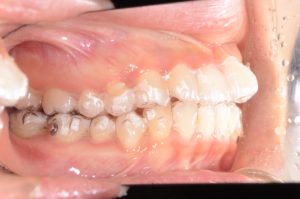

【スプリント治療後】

歯並びは変わっていませんが、顎の位置が正常に安定したことで

噛み合わせの位置が変化していることが分かります。

正しい位置で咬めるようになったためインビザラインに移行します。